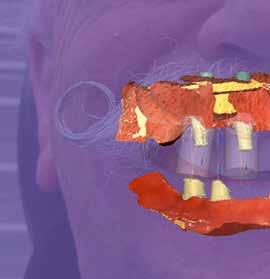

A laboratóriumban az összes adatot összefűztük egy „digitális pácienssé” a darmstadti exocad DentaCad rendszerében. Az állcsontokat a vesztibuláris fogsorbeolvasással illesztettük térben egymáshoz (3. kép). Az implantátumok helyzetét a fejek mutatták meg. A külön beszkennelt fogsorokat pedig mock-up-ként tudtuk használni a tervezés során (4. kép). A páciens portréját rávetítettük a frontra, így segítve az esztétikai ellenőrzést (5. kép)

5. kép: A fogorvos által küldött 3D szkennelésű adatokból áll össze a „virtuális páciens”